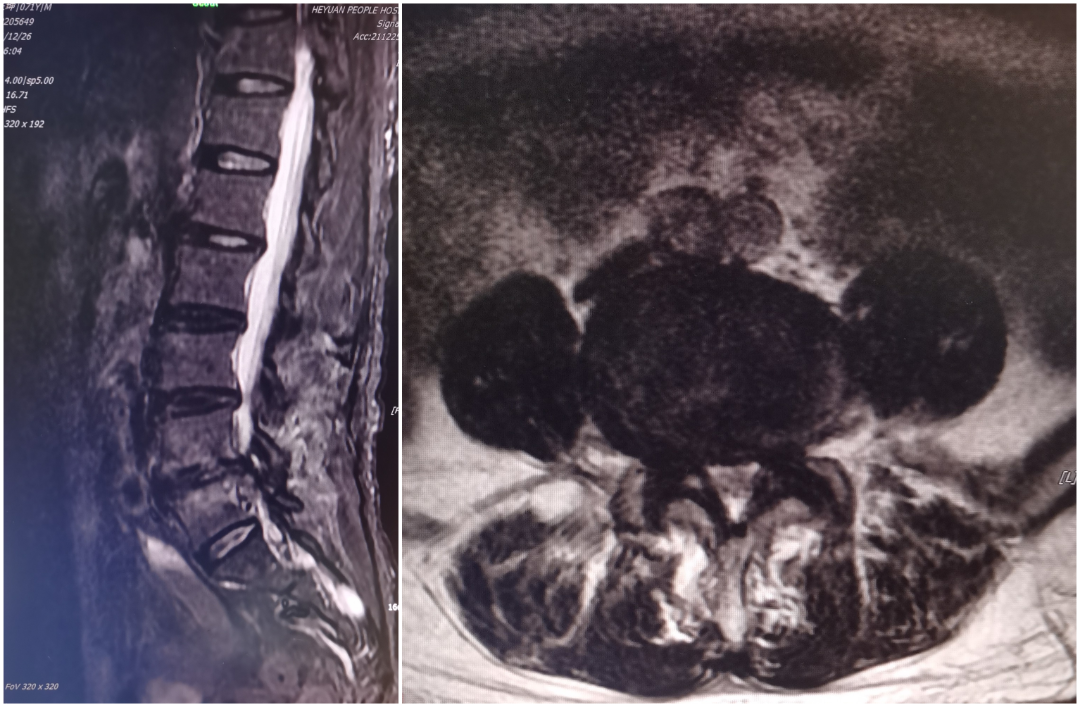

UBE镜下融合经皮固定(Ulif)

黄某,71岁男性患者,因反复腰部疼痛3年余,再发加重1周入院,查体:脊柱生理弯曲存在,腰部无明显肿胀,未扪及明显台阶感,下腰段椎间隙压痛,椎旁肌稍压痛及叩击痛,双下肢萎缩,右侧直腿抬高试验及加强试验阳性,右足第1趾背伸及跖屈伸肌力减弱,右大腿外侧、小腿外侧、后侧及足背外侧感觉麻木,左下肢感觉正常,结合辅助检查,诊断:腰椎管狭窄症:腰4/5椎间盘突出,于全麻下行经单侧双通道脊柱内镜下腰4/5椎板开窗减压、腰4/5椎间盘摘除、椎间cage植骨融合、经皮钉棒系统内固定术。患者术后腰部及双下肢麻痛症状明显改善。

术前影像学

术中透视、术后复查